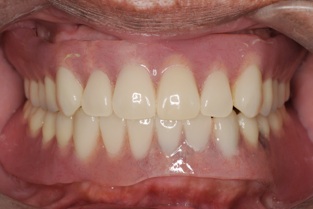

マグネットをつけているので大幅に義歯の面積を縮小することが可能になりました。

患者様も違和感がないと大喜びです。